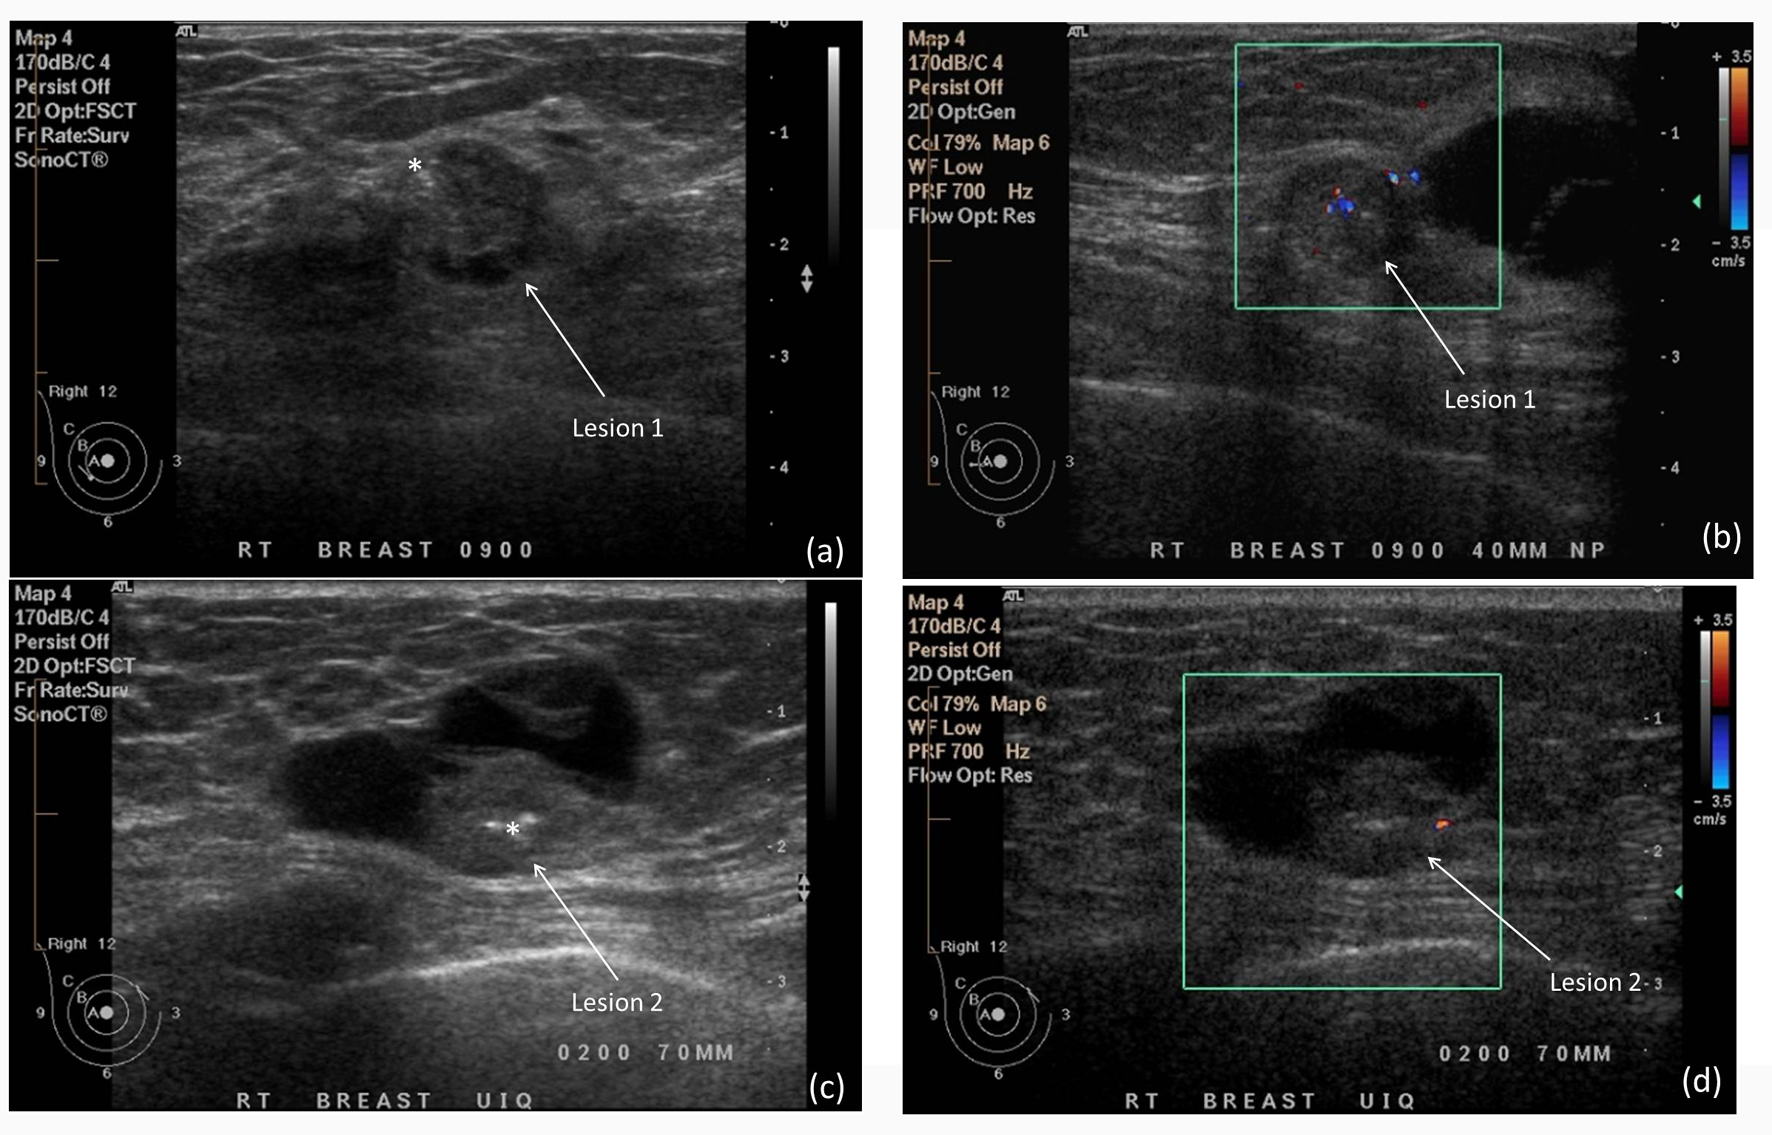

El ultrasonido mamario es especialmente eficaz para identificar quistes y tumores en las mamas. Los quistes son sacos llenos de líquido que pueden formarse dentro de los senos, y generalmente no son cancerosos. Sin embargo, su presencia puede ser un motivo de preocupación para las pacientes, y es crucial diferenciarlos de las masas sólidas, que podrían ser indicativas de cáncer.

El ultrasonido permite a los médicos observar la forma, el tamaño y la composición de los bultos, lo que facilita la identificación de si son quistes benignos o tumores sólidos. Esto ayuda a los profesionales de la salud a decidir si se necesitan pruebas adicionales, como una biopsia, para obtener un diagnóstico definitivo.

Evaluación de Lesiones Dificiles de Detectar

En mujeres jóvenes o aquellas con senos densos, el tejido mamario puede dificultar la visibilidad de algunas masas en una mamografía. Sin embargo, el ultrasonido mamario proporciona una visión más clara de los tejidos densos y puede detectar lesiones que no son visibles en las radiografías. Esto es especialmente importante para identificar cambios tempranos en los senos que podrían pasar desapercibidos en otros exámenes.

El ultrasonido mamario también se utiliza para el seguimiento de afecciones previamente diagnosticadas, como quistes o tumores. Mediante exámenes periódicos, los médicos pueden observar cambios en el tamaño o la forma de las lesiones, lo que les permite detectar cualquier signo de malignidad a tiempo. Esto es crucial para asegurar que no haya un desarrollo de cáncer o cualquier otra afección preocupante.

En situaciones donde otros exámenes no proporcionan información suficiente, el ultrasonido mamario se utiliza como una herramienta complementaria. Por ejemplo, si se encuentra un nódulo durante un autoexamen de mama o en un examen físico, pero no se obtiene una imagen clara a través de la mamografía, el ultrasonido puede ofrecer una evaluación adicional. Esta capacidad para complementar otras técnicas hace que el ultrasonido sea una herramienta valiosa para los médicos en la evaluación de posibles afecciones mamarias.